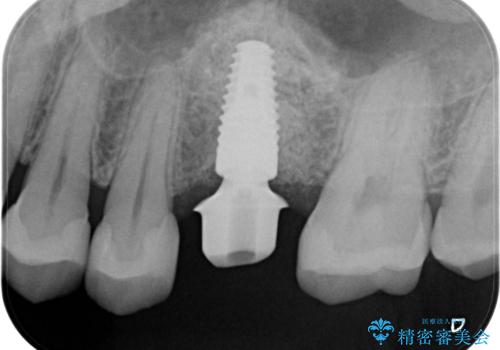

- 左上6:歯槽堤保存術/110,000円 サイナスリフト/110,000円 骨造成/55,000円 静脈内鎮静/55,000円 インプラント体/242,000円 チタンカスタムアバットメント/110,000円 仮歯/22,000円 ジルコニアクラウン/121,000円 合計825,000円 左上5:セラミックインレー/77,000円費用は治療当時の料金となります

良い位置に良い方向でインプラントを埋入することができました。

手前の歯の虫歯もセラミックインレーで精度よく治療を行いました。